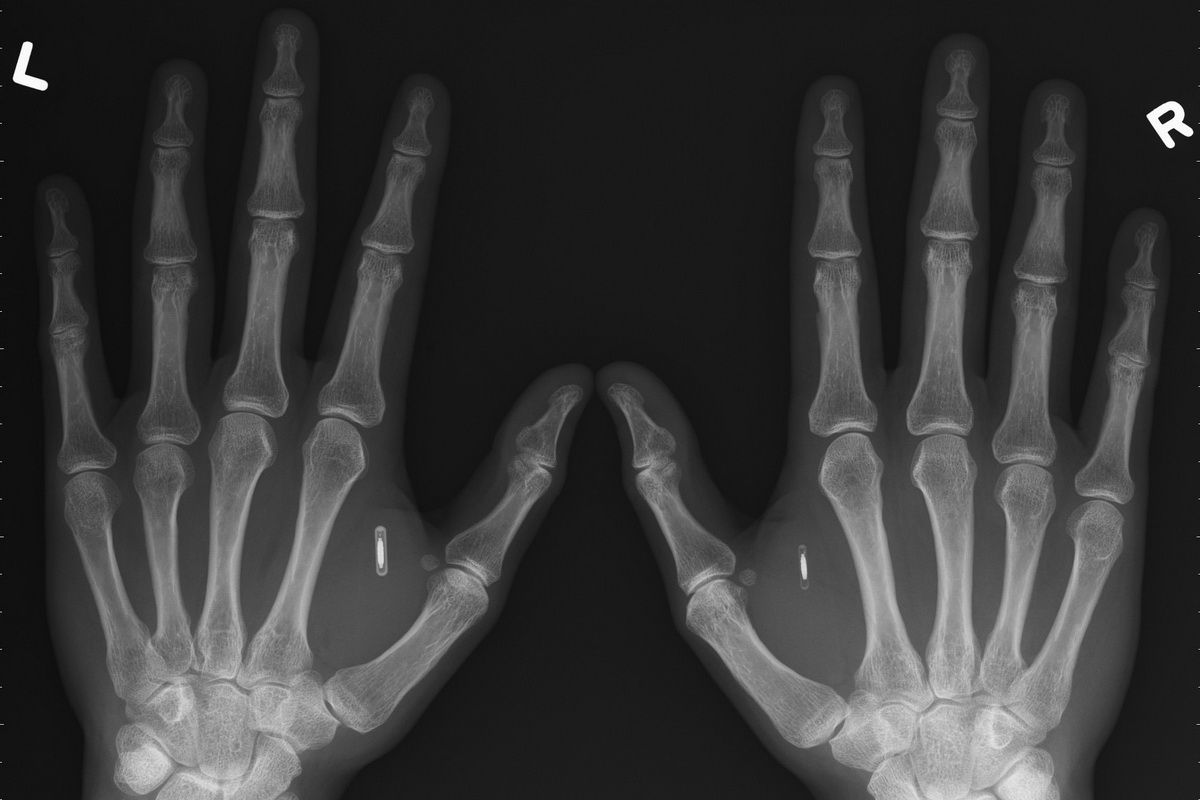

V ľavej ruke nosí NFC čip, ktorý si kúpil od spoločnosti Dangerous Things za 100 dolárov. Tí mu poslali 13,56 MHz NTAG216RFID čip, ktorý je plne kompatibilný s NFC uložený v sterilnej injekčnej striekačke. Čip je dlhý 12 milimetrov a široký 2 milimetre. No a aké to má presne využitie?

Implantácia čipu